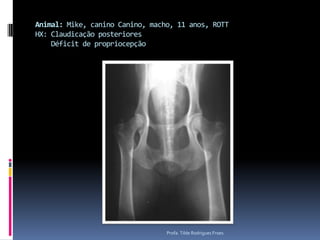

Animal: Mike, canino Canino, macho, 11 anos, ROTTHX: Claudicação posteriores    Déficit de propriocepçãoProfa. Tilde Rodrigues Froes

Animal: Mike, caninoCanino, macho, 11 anos, ROTTHX: Claudicação posteriores Déficit de propriocepçãoProfa. Tilde Rodrigues Froes